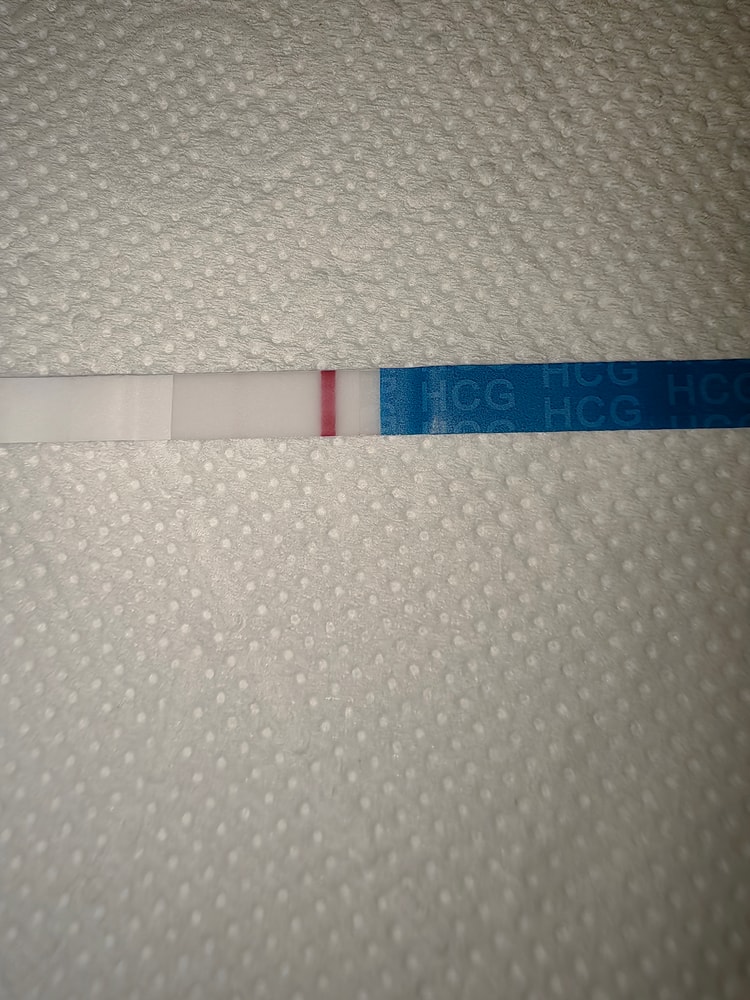

Вчера клиаблю непонятно что мне нарисовал, поэтому сегодня я снова сделала тест))

фоткала под разными освещениями. Очень уж хочется, чтобы кто-то кроме меня тоже увидел полоску🤣🤣 фотки, где теста два - верхний это вчерашний утренний, а нижний сегодняшний. Видите ли вы что-нибудь?🥺

На нижнем вижу //